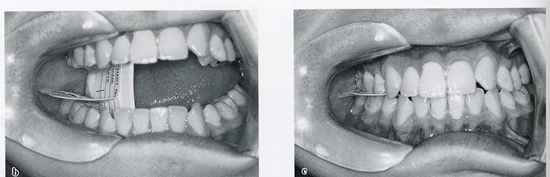

口腔内写真では、問題がなさそうに見えますが、バイトウイング(咬翼)法レントゲンを撮ったところ、歯の間に虫歯があることがわかりました。より早く異常を見つけることができました。